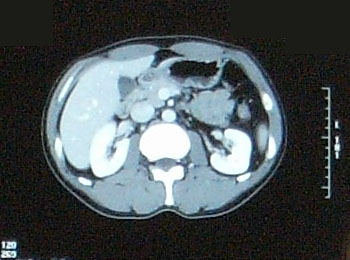

でも、髪質は脱毛前とは全く異なり、硬く、クセの強い、ゴワゴワしたものだった。 いろいろな人の体験記を読んでいたので、そうなるかもしれないこともわかっていたし、実際に抗癌剤治療をしたのだから「ま、そうだろうな」と思っていた。 でも、ここ最近ちょっと様子が変わったらしい。 今日、再び美容室に行った。 美容師さん:「少し柔らかくなったような・・以前はもっとこう・・何と言うか・・」 自分:「硬くてゴワゴワしてましたよね。」 少し髪質が柔らかくなってきたみたい。 いや、治療前の髪質に戻り始めたかな。 髪で風を感じるようになってきたのがちょっぴりうれしい最近です。 先日撮影したCT、採血結果を聞いてきました。 【画像】:変化なし 【HCGΒ】:0.1> 普通に仕事をして、普通に疲れてますが、検査的には問題なし。 この病気、わりと仕事現役世代が多いと思うのですが、みなさん治療後はバリバリ働いているのだろうか。 それで大丈夫なのだろうか。 それにしてもCT画像を見るのはおもしろい。 生きたまま自分の内部が見れるんだから。 毎回診察時に「写真撮っていいですか?」が恒例になってきてる。 先生も「あぁ、どうぞ(苦笑)。あ、撮るならこっちかな。」とか言って該当するほうのフィルムを移動してくれる(笑)。 そうだ、この日は入院時にお世話になった看護士の○澤さんが外来で助手をしてた。 ほとんど話ができなかったけど、この場をかりて 「大変お世話になりました。本当に感謝してます。」